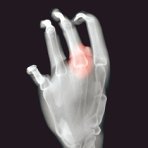

Ein neuartiger monoklonaler Antikörper erweitert künftig die Behandlungsmöglichkeiten bei rheumatoider Arthritis. Der Wirkstoff Tocilizumab hemmt den Botenstoff Interleukin-6 des Immunsystems. Bei dieser Krankheit attackiert das fehlgeleitete Immunsystem die eigenen Gelenke und andere Gewebe. Zwar lässt sich das oft mit sogenannten TNF-α-Hemmstoffen erfolgreich behandeln, manche Patienten sprechen jedoch nicht auf diese Mittel an. Hier biete Tocilizumab als völlig neuer Therapieansatz eine Alternative, teilte der Hersteller Roche zur Einführung in Köln mit. Das Präparat namens Roactemra® wird einmal monatlich als Infusion verabreicht. In Studien hat es sich ähnlich wirksam wie die TNF-α-Hemmstoffe erwiesen. Tocilizumab ist EU-weit für Patienten zugelassen, bei denen andere Arzneimittel versagt haben.